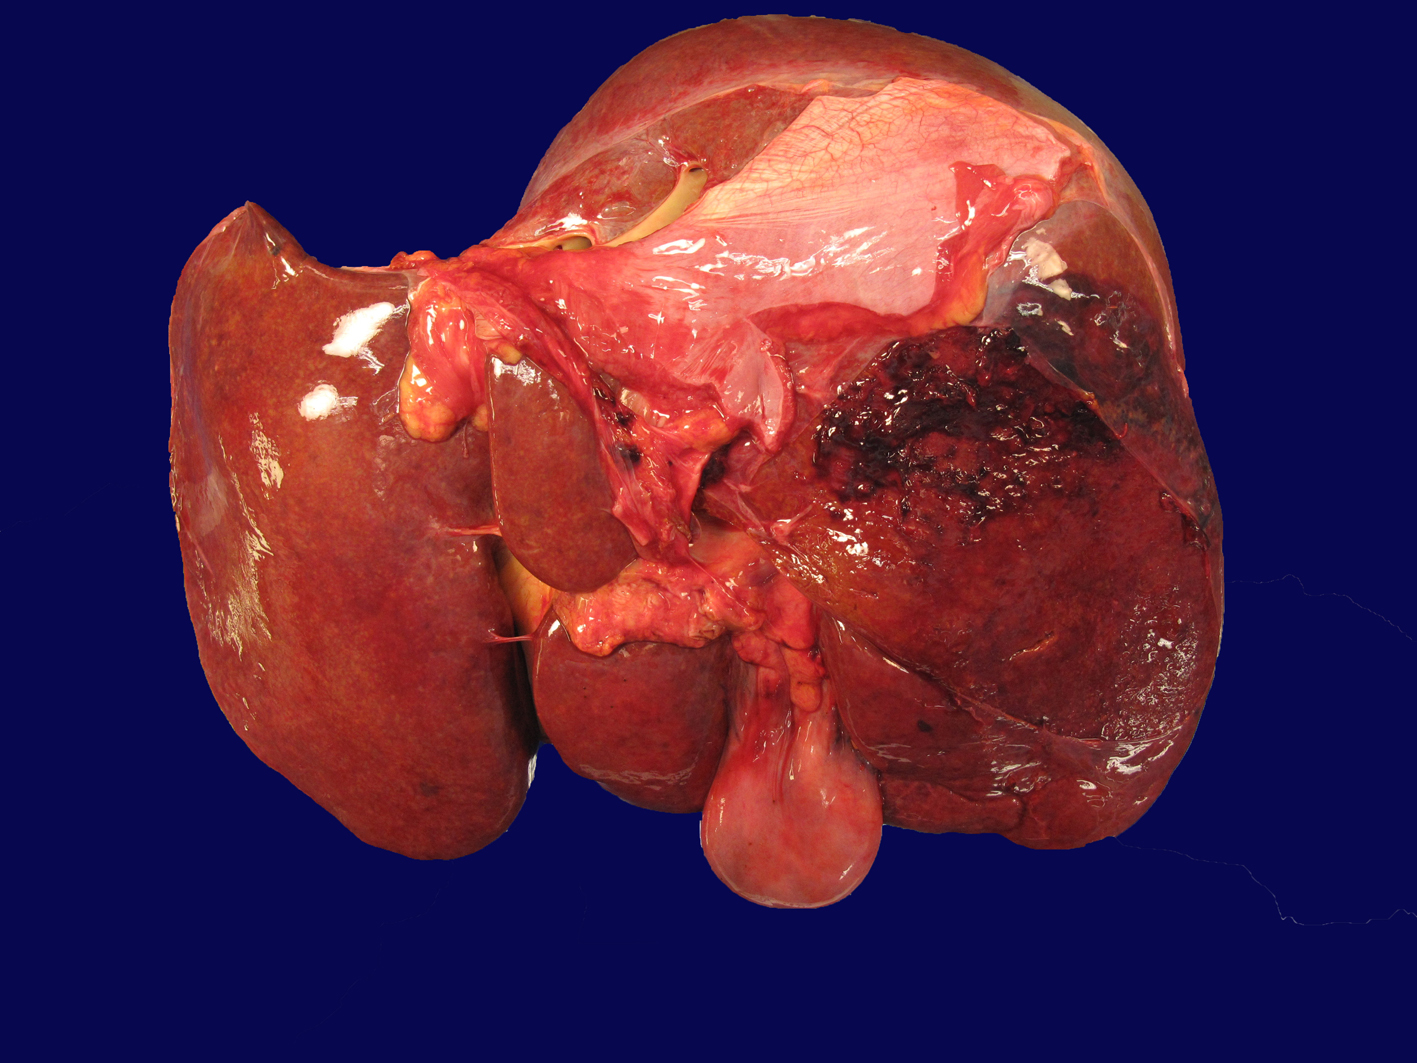

Autopsy demonstrated an area of capsular and subcapsular parenchymal disruption (Fig. 2) with hemorrhage on the posterior surface of the right liver lobe with an associated peripherally located intra-hepatic hematoma (6.5 × 5.5 × 5 cm). Additionally, two intact cavernous hemangiomas (5 and 1.5 cm) were found in the right lobe of the liver and an intact biopsy site was identified on the surface of the left liver. The liver was examined extensively for a needle tract as evidence of hemorrhage from the transjugular biopsy, but none was found. Histologically, the hematoma and areas of hemorrhage contained numerous CD56+/CD7+ atypical lymphocytes, consistent with the patient’s NK cell leukemia.

![]() Click for large image | Figure 2. Liver with capsular and subcapsular parenchymal disruption on posterior surface of right lobe. This area was associated with an underlying intra-hepatic hematoma (6.5 × 5.5 × 5 cm). |

At autopsy, atypical LGLs were found to involve the bone marrow, lungs, duodenum and liver. Additionally, a large hematoma associated with capsular and subcapsular disruption was identified in the right liver lobe, consistent with hepatic capsular rupture that was the likely cause of hemodynamic compromise and death. We were not able to demonstrate ANKL involvement of the spleen due to extensive necrosis at the time of autopsy, but given the patient’s significant splenomegaly and diffuse organ involvement by ANKL, it is likely that neoplastic NK cells diffusely infiltrated the spleen.

Interestingly, spontaneous hemorrhagic complications have been reported to occur in ANKL. Okuno et al reported three cases of ANKL with lethal intestinal and cerebral hemorrhage, and Gao et al reported a case of ANKL presenting with splenic rupture [4, 11]. Our patient is the first reported case of spontaneous hepatic rupture in this disease. We considered several possible factors that may have contributed to the spontaneous hepatic rupture in our case. First, massive parenchymal infiltration by malignant cells in the liver and spleen may have led to capsule stretching, and ultimately, capsular disruption [3, 6, 11]. Second, our patient’s concomitant coagulopathy, as is commonly reported in this disease may have also been a contributing factor [4, 8, 11]. Additionally, the liver biopsy revealed features consistent with L-asparaginase toxicity, which may have also contributed to the development of coagulopathy. Finally, studies have shown that neoplastic NK cells are angio-invasive with the ability to cause massive necrosis through both vascular obstruction and diffuse infiltration of vessel walls [3, 4, 8]. Although our patient underwent two liver biopsies prior to the hepatic rupture, the first liver biopsy site (located in the opposite lobe) was intact, and the second biopsy was transjugular, distant from the peripherally located hematoma without an identifiable needle track, making the biopsies an unlikely source for subcapsular hemorrhage.